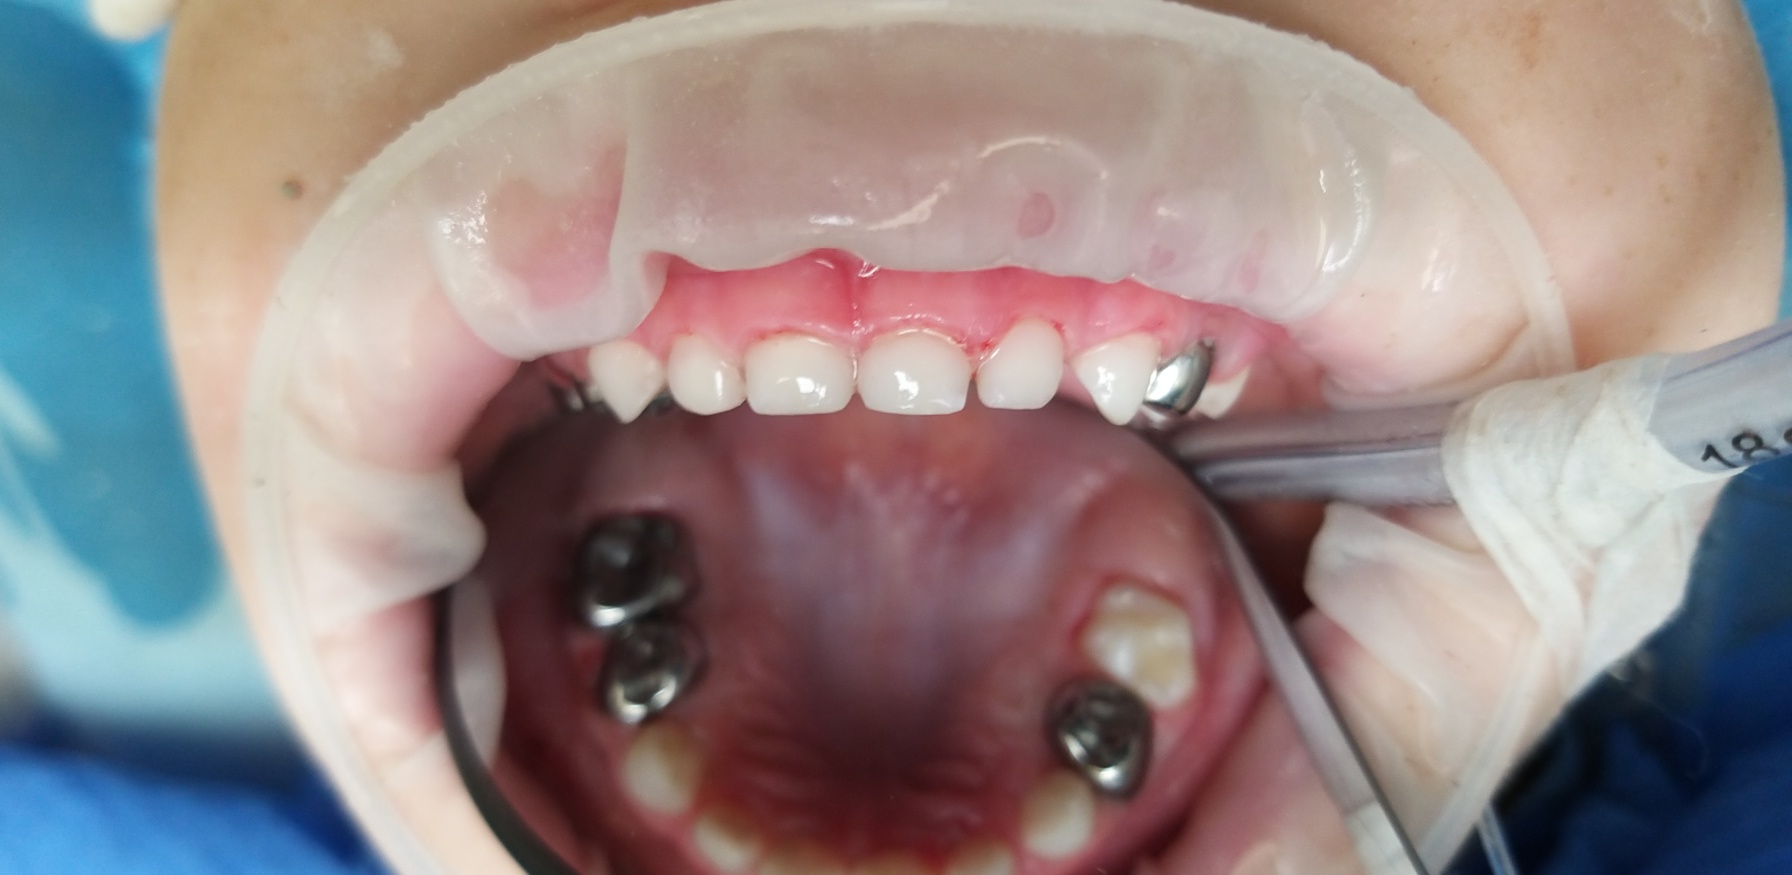

Лікар стоматолог - терапевт